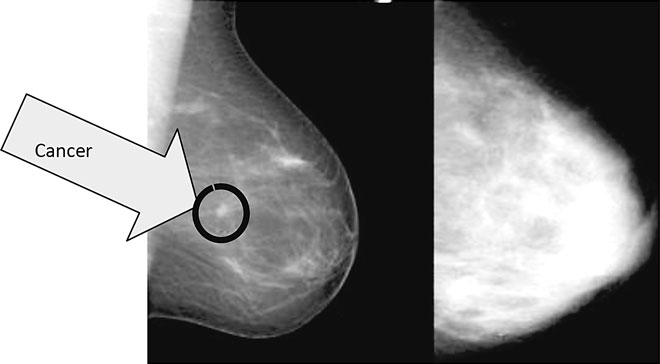

Chances are great that you just might be dense — in your breasts. Dense breast tissue is comprised of less fat and more connective tissue, which appears white on a mammogram. Cancer also appears white, which makes spotting cancer in dense breast tissue more challenging than in fatty tissue.

On the left is a mamogram of a fatty breast. The mammogram on the right shows a very dense breast. It too has a cancer in roughly the same location but I challenge you to find it.